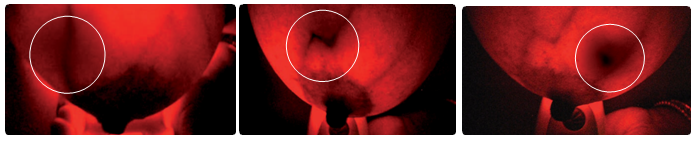

ブレストライトの光は特定の波長の赤い可視光で、この光は乳房の軟組織を透過します。光が透過することで、乳房の内側が赤く半透明に映ります。また、この波長の光は血液中の赤血球のヘモグロビンに吸収されるので、血管は黒い線のように映ります。

早期の悪性腫瘍では、腫瘍の周りに血管が増殖することが認められています。ブレストライトでは血管が多く集まっている部分は暗い影のように映るので、悪性腫瘍の周りに増殖した血管も暗く映ります。よってこの影を「異常の疑い」として検知することができます。

ブレストライトを使用した場合、血流の増加は、暗い影や暗い部分として映ります。

- 光が当たった部分が赤く半透明に映り、正常な静脈や血管は、暗い線のように映ります。

ある種のがんの初期段階では、がんへの血流増加が起こるものがあります。ブレストライトでは、このような血流の増加が暗い部分や影のように映ります。